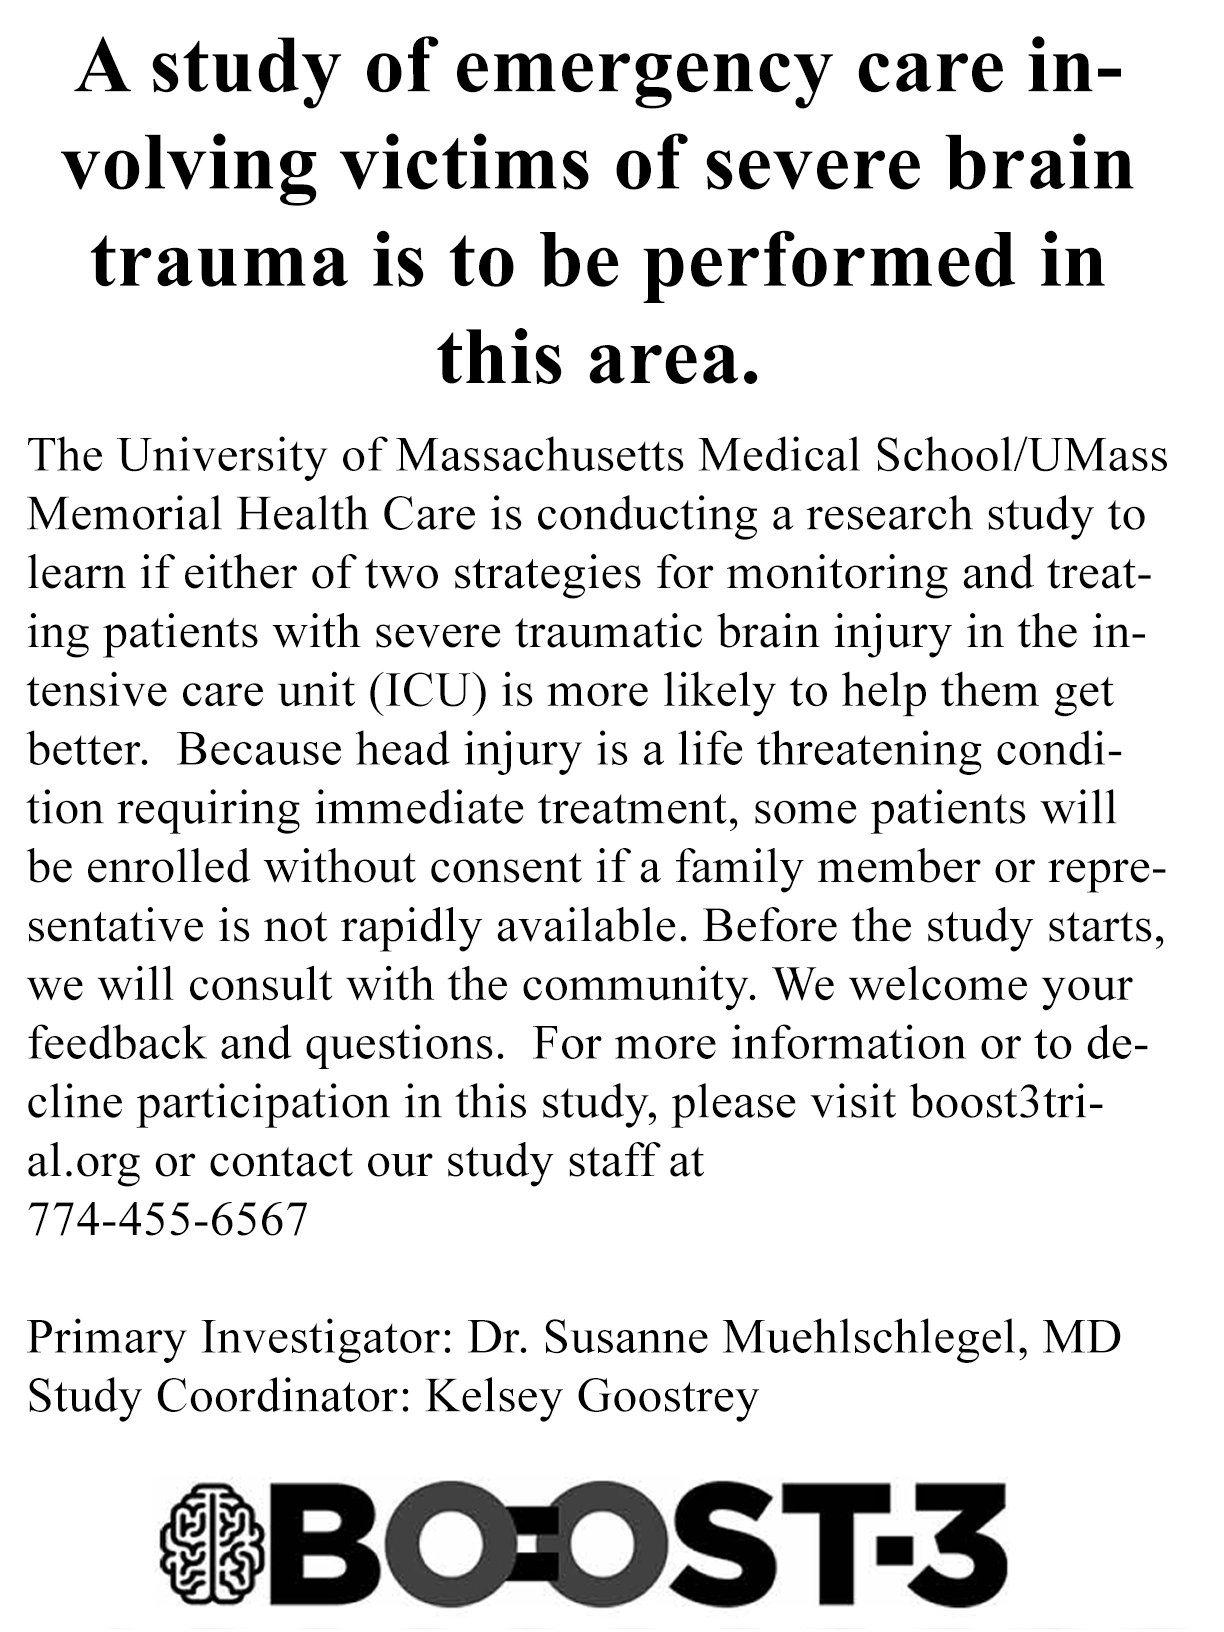

Ongoing Research

Our mission is simple: To improve the care of critically ill patients with neurologic emergencies. Our clinical research laboratory employs cutting edge population research, clinical trials and qualitative research.